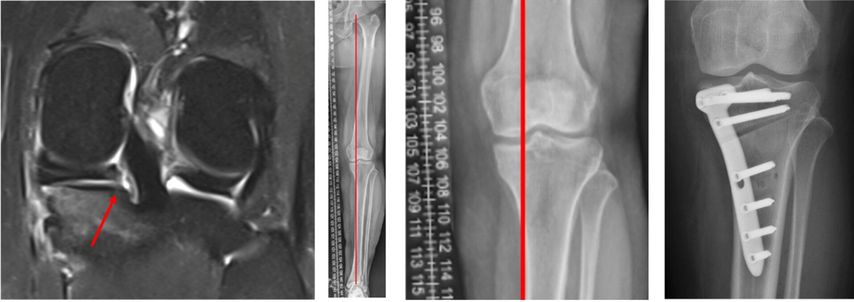

Dies verdeutlicht der Fall einer 46 Jahre alten Patientin mit atraumatischen Schmerzen im medialen Kniegelenk links (Abb. 2). In der präoperativen MRT-Diagnostik zeigt sich der degenerative Innenmeniskuswurzelriss (linkes Bild, Pfeil). In der präoperativen Röntgen-Ganzbeinaufnahme im Stehen ist ein Varus-Malalignment von 4° zu erkennen (Bilder in der Mitte). Es erfolgte eine arthroskopische Innenmeniskuswurzelrefixation mittels transtibialer Auszugsnaht, kombiniert mit einer valgisierenden medial öffnenden hohen tibialen Osteotomie (rechts).

Abweichungen von der Beinachse und Verlust des Meniskus erhöhen beide gemeinsam das Risiko für eine Arthrose. «Wir haben speziell für Meniskusrisse bisher keine belastbare Evidenz, ab wann man die Beinachse operativ korrigieren sollte», sagte Behrendt. Eine Ausnahme scheinen Wurzelverletzungen zu sein. In einer Studie aus Seoul17 mit 476 Patienten, die wegen einer Pathologie am Innenmeniskus arthroskopiert wurden, hatten diejenigen mit Wurzelläsion eine deutlich ausgeprägtere Varusfehlstellung als Patienten mit anderen Rissformen (4,5±3,4° versus 2,4±2,7°). Orthopäden von der Mayo Clinic in Rochester18 empfehlen, bei Meniskuswurzelrissen nach einem Algorithmus vorzugehen (Abb.2). Viele Jahre wurde eine Achsenfehlstellung von >5° als korrekturbedürftig angesehen. Auf Grundlage einer Studie von 201319 und von Daten aus dem Knorpelregister der DGOU20,21 empfiehlt die Arbeitsgemeinschaft Klinische Geweberegeneration der DGOU, die Beinachse bereits ab einer Fehlstellung von 3° zu korrigieren.22 Eine Beinachsenkorrektur sei immer eine sehr individuelle Entscheidung, über die der Patient gut aufgeklärt werden müsse, sagte Behrendt.«Bei der Weiterentwicklung einer bereits eingetretenen Arthrose spielt die Achse einen sehr entscheidenden Einflussfaktor. Dies sollte grosszügig mit in das diagnostische Workup integriert werden.»